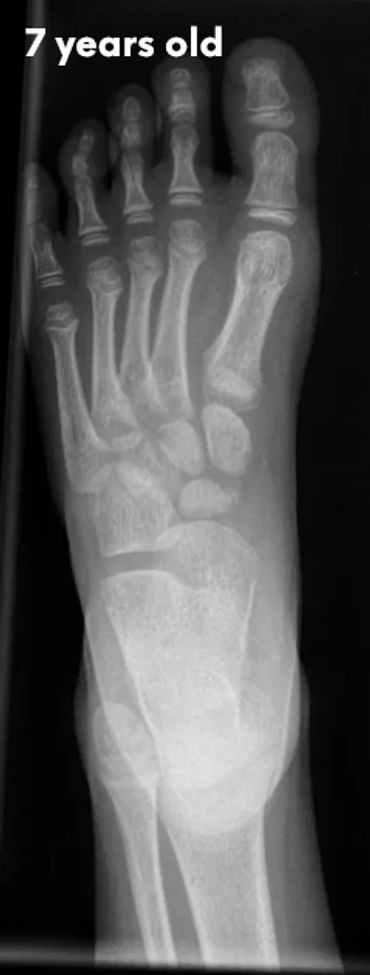

Let's check what their foot bones look like.

Pictures below will let you understand how babies' feet are developed.

Dear parents, children’s feet are developing structures, and the absence of an arch is a typical stage of development. The developing foot is not structurally ‘flat’; it is a highly compliant and plastic, that can respond to multiple factors, many of which we do not understand. Detailed X-RAY pictures above, let us understand that babies' foot bones are not connected till the teen years. Only at the age of 14, we may consider that the bones in the feet are developed and have reached their connections.